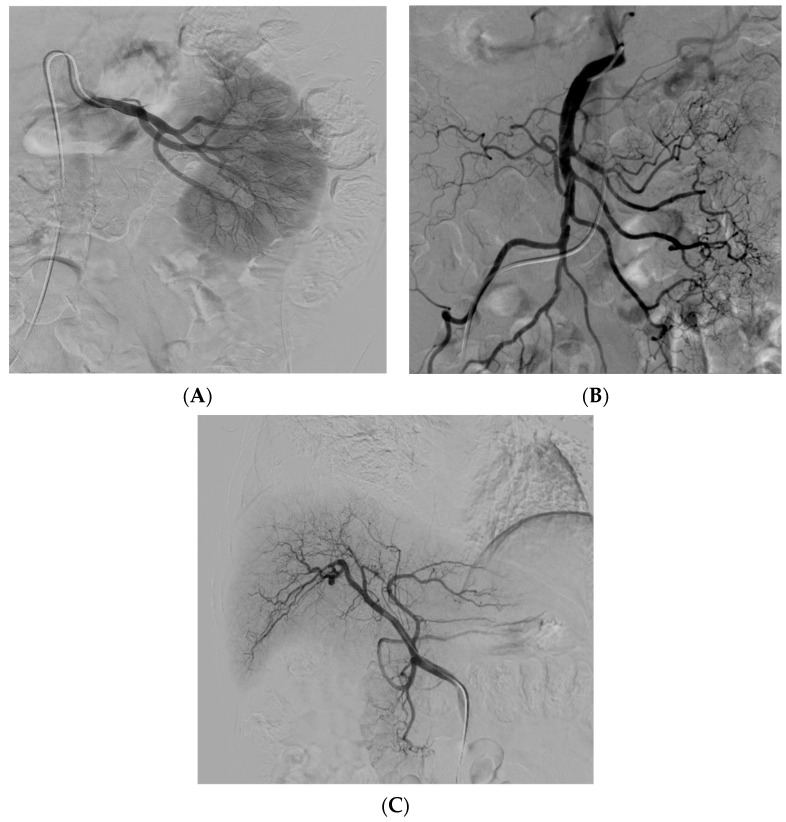

經(jīng)動(dòng)脈干細(xì)胞注射(TASI)可能被認(rèn)為是一種理想的選擇性遞送方法,在所需器官中具有最佳分布和高干細(xì)胞濃度。在組織取樣和干細(xì)胞分離處理(自體或異體)之后,該過(guò)程基本上包括通過(guò)動(dòng)脈通路(最常見(jiàn)的是股動(dòng)脈)引入導(dǎo)管。然后,在熒光鏡和造影劑引導(dǎo)下,將導(dǎo)管放置在所需的供血?jiǎng)用}(肝動(dòng)脈、腸系膜動(dòng)脈或腎動(dòng)脈)中,以進(jìn)行隨后的干細(xì)胞注射。圖2)。

圖2:腎 (?A?)、腸系膜上動(dòng)脈 (?B?) 和肝動(dòng)脈 (?C?) 的血管造影插管

圖2

導(dǎo)管定位確保對(duì)所需組織進(jìn)行選擇性治療,避免非目標(biāo)干細(xì)胞輸注。